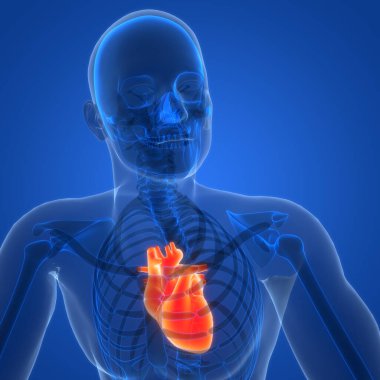

Kalbin anatomik incelemesi. Kalp sorunları, kalp krizi. Ameliyat mı? 3D görüntüleme. Siluet. Kalp, dolaşım sisteminin kan damarlarına kan pompalayan kaslı bir organdır.